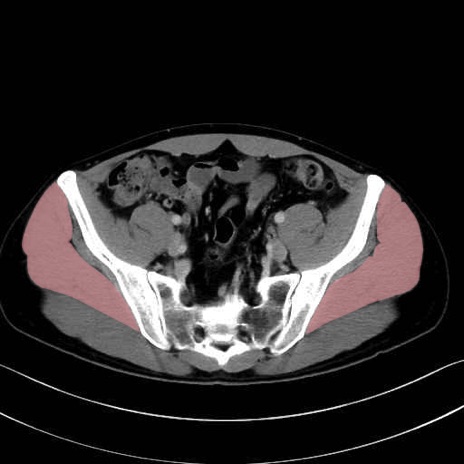

中殿筋 (Gluteus medius)